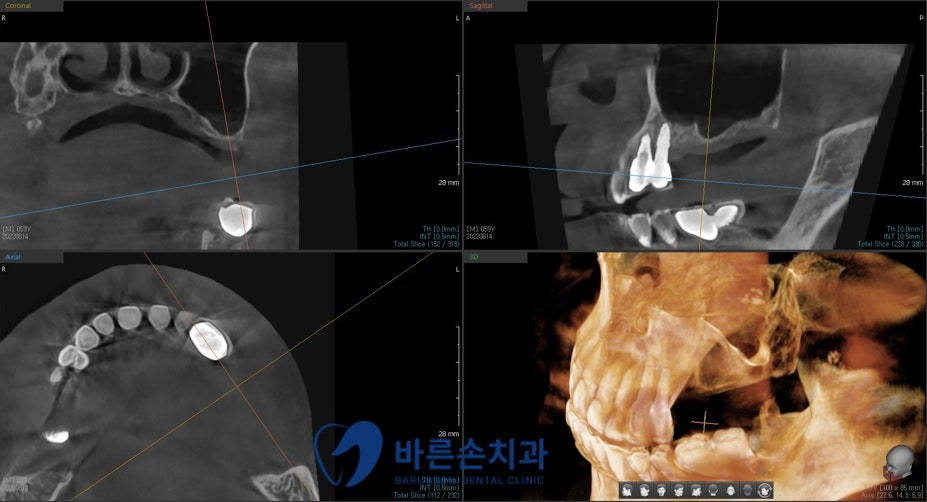

정확한 진단을 위해 엑스레이 촬영을 시행하였습니다

파노라마와 3D-CT 촬영 결과

장기간의 치아 상실로 인해

상악동이 많이 내려와 있는 게 보이네요

그로 인해 임플란트를 식립하기 위한 뼈의 양이 부족하기 때문에

임플란트 식립 시 상악동 거상술과 치조골 이식을 함께 진행하기로 했습니다